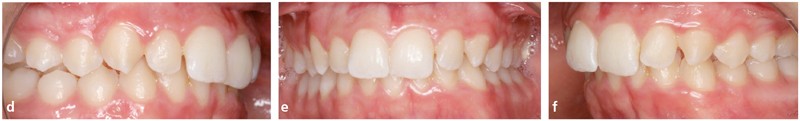

Analyse dentaire : les arcades dentaires sont asymétriques avec une Classe II molaire et canine mais plus importantes à gauche (fig. 1d, e et f).